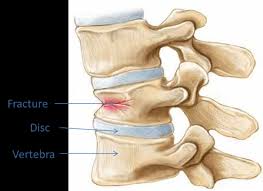

Compression fractures of the spine generally occur from too much pressure on the vertebral body. This usually results from a combination of bending forward i suffered a compression fracture of the l2/l3/l4 vertebrae six years ago, and now i'm suffering with tremendous pain, discomfort and mobility. Vertebral compression fractures | american association of neurological surgeons. Vertebral compression fractures can be caused by a variety of reasons; A compression fracture refers to a vertebral bone in the spine abrupting or collapsing as a result of pressure/degeneration of the spinal bones.

Over the weekend i have been experiencing pins and needles in my right hand and arm, a sensation of someone pouring cold water on my left thigh and. The fracture line breaches both the anterior and posterior vertebral body cortex and the anterior superior endplate. A compression fracture is a type of fracture or break in your vertebrae. They often occur in the upper lumbar segments as well, such as l1. In the lumbar region, where the most axial load is, the vertebrae of level l (1 and 2) are injured. Compression fractures are the most common type of fracture affecting the spine. Compression fractures of the spine generally occur from too much pressure on the vertebral body. A compression fracture of a spine bone (vertebra) causes the bone to collapse in height. The doctor suggested bracing for three. Individuals that have been diagnosed with osteoporosis are very prone to developing small fractures in the spine, eventually leading to a compression fracture. The vertebrae are the bones in your back that are stacked on top of each other compression fractures can cause the vertebrae to collapse, making them shorter in height. Apply the one that makes the injury feel better. One and a half years back i got a compressed l1 fracture as a result of a car accident.

The fracture looks like more of a compression fracture than a burst fracture (there is no retropulsion of the l1 body posteriorly). Applying heat in the first few days after an injury draws more blood to the injury site, thus. In very severe compression fractures, the back of the vertebral body may actually protrude into the spinal canal and put pressure on the spinal cord. First, the fracture itself can cause significant pain, and media gallery. A compression fracture that occurs suddenly can be very painful, but a compression fracture that occurs gradually may cause pain only gradually.